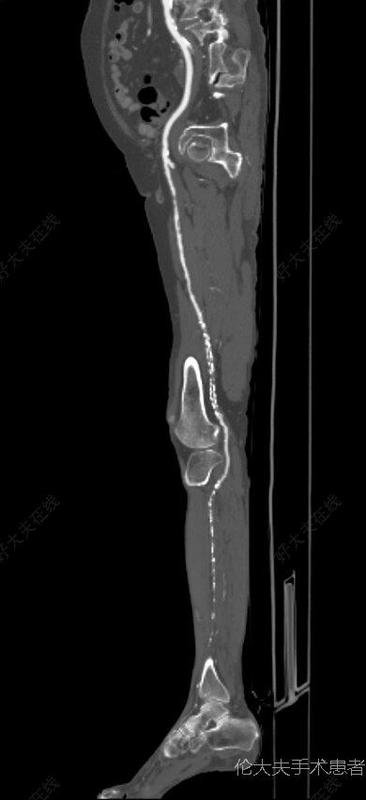

治療前老年女性,長期糖尿病史,癥狀表現(xiàn)為重度跛行,術(shù)前ABI0.4治療中造影與CTA一致,股淺近端一處點式狹窄,遠端至腘P1段嚴重鈣化閉塞。導絲雖然真腔通過,但是擴張后仍然出現(xiàn)限流性夾層,無奈之下行支架置入。治療后治療后即刻術(shù)后效果滿意